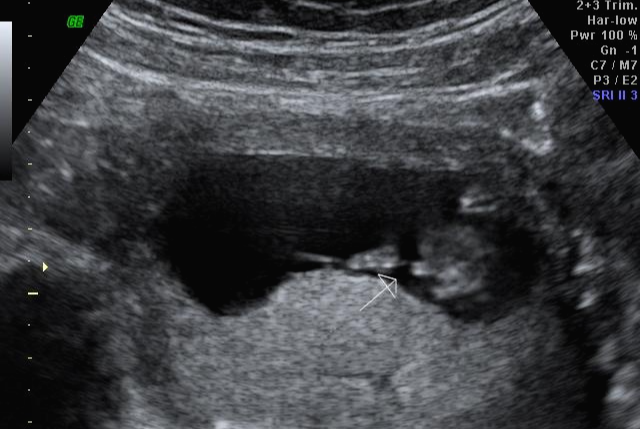

한 달 뒤인 17차 때 다시 사설로 가서 초음파 검사를 받았는데 검사해주시는 분 께서 한참을 보시더라고요~ 그러면서 어떻게 보면 딸 같다고 하셔서... 응? 100프로 아들이라 해서... 다 아들껄로 준비하고 있는데.. 무슨 소리지? 하고 다시 한번 봐달라고 하니 아들이라 하시면서 위에 초음파를 보여주셨어요!

한데 기분이 참 찝찝했어요~ 뭔가 숨기고 있는 듯한.. 정확하지 않는 듯한 느낌 ㅋㅋㅋ... 그래서 임신 17주 차부터 아이 용품 구매하는 걸 중단하고 병원에서 20주 차 정밀 초음파 검사를 기다려 보기로... 가족도 다 아들로 알고 있고 벌써 아들 꺼 처럼 보이는 용품들로 준비했기 때문에 성별 반전이 없기를 기대했어요 ㅠㅠ